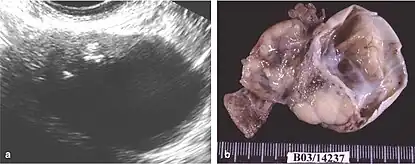

Mature cystic teratoma (MCT), affecting women in 10–20% of cases during their lifetime, is characterized by benign mature cystic teratomas—an intriguing subject in gynecological pathology.[8][3] These non-cancerous tumors, originating from at least two embryonic germ cell layers, exhibit a complex interplay of developmental pathways, stemming from singular germ cells or the complexities of meiosis I and II failure.[9][10] Internally lined with squamous epithelium and externally connected to the ovarian stroma, mature cystic teratomas contain diverse fluids such as sebaceous, serous, or mucinous.

Although the majority of MCT cases are non-malignant, approximately 0.17-2% may undergo malignant transformation, with squamous cell carcinoma being the most prevalent, constituting 80% of such transformations.[11] The clinical presentation of oSCC development within MCT lacks specificity, often resulting in the inadvertent discovery of early-stage tumors during routine examinations or postoperative assessments. In advanced cases, patients may exhibit palpable masses, abdominal swelling, and pain, potentially leading to acute abdominal complications due to tumor involvement.[10][12][4]